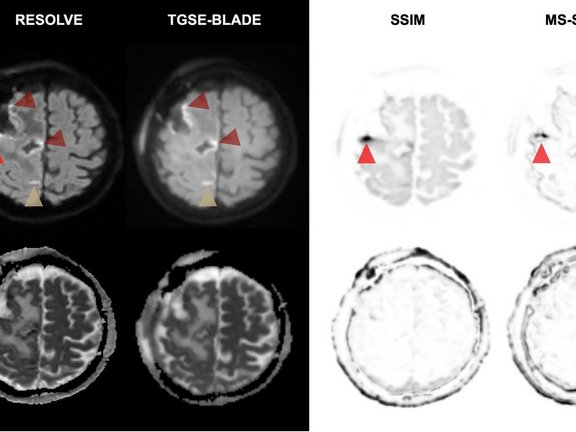

Die Studie: Vergleich von TGSE-BLADE und RESOLVE

• RESOLVE DWI: Eine gängige Technik, bei der die Datenerfassung segmentiert wird, um bestimmte Verzerrungen zu reduzieren.

• TGSE-BLADE DWI: Eine Nicht-EPI-Technik mit „radialer“ Datenerfassung, die unempfindlich gegenüber Magnetfeldinhomogenitäten ist.

Die Studie zeigt, dass TGSE-BLADE DWI RESOLVE in mehreren entscheidenden Punkten überlegen war:

• Reduzierte Verzerrung: TGSE-BLADE zeigte signifikant weniger geometrische Verzerrungen und Artefakte im Bereich der Resektion als RESOLVE (p < 0,001).

• Höhere Genauigkeit: Die Messungen des Resektionsareals in TGSE-BLADE-Bildern stimmten eng mit den T1-gewichteten Referenzaufnahmen überein, während RESOLVE aufgrund von Bildverzerrungen signifikante Abweichungen aufwies.

• Diagnostische Sicherheit: Neuroradiolog:innen berichteten über eine signifikant höhere diagnostische Sicherheit und eine bessere Gesamtbildqualität bei Verwendung von TGSE-BLADE.

• Abwägungen: Obwohl RESOLVE DWI ein leicht höheres Signal-Rausch-Verhältnis (SNR) aufwies, machte die Klarheit und Verzerrungsfreiheit von TGSE-BLADE diese Technik zum überlegenen Instrument für die klinische Beurteilung.